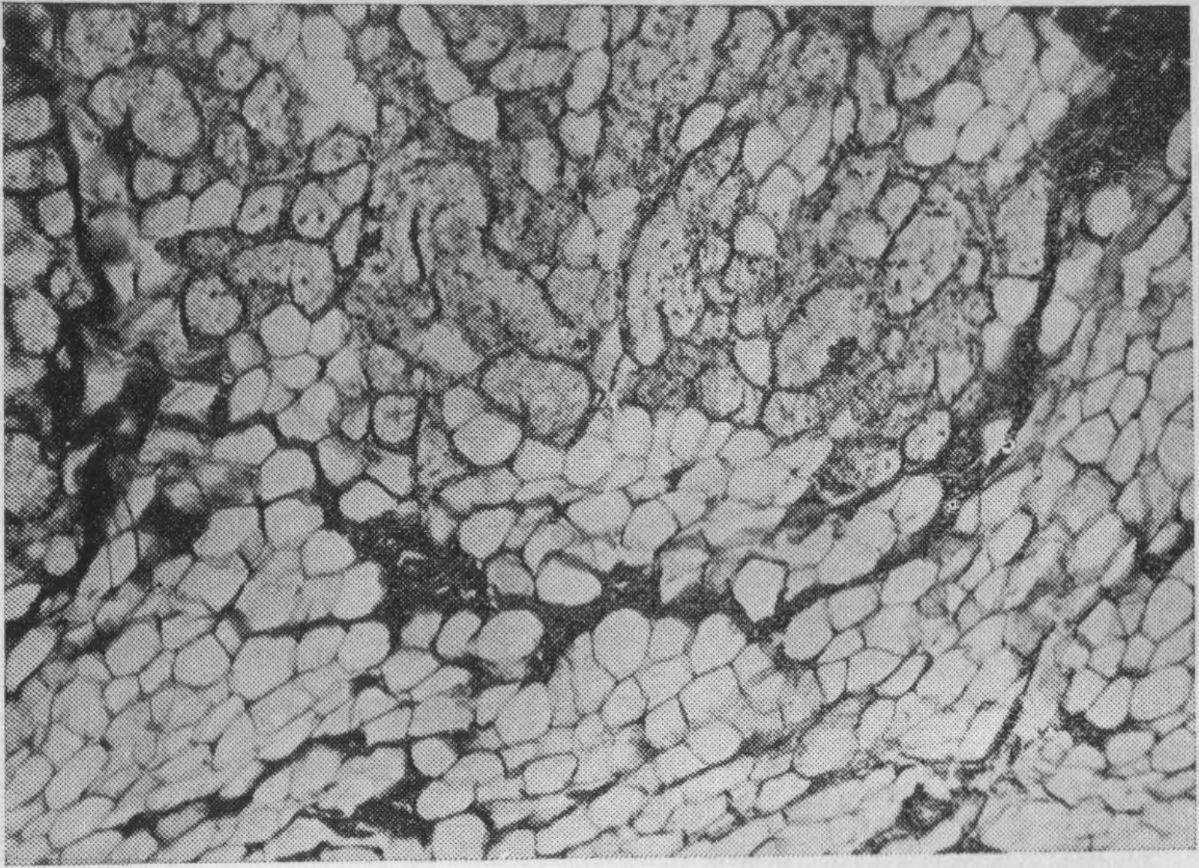

Рис. 39. Слизистая оболочка твердого неба мужчины 76 лет. Липоматоз стромы желез. Окраска пикрофуксином. Х75 (Иванова H. С.).

Обширные инфильтрированные участки желез замещались жировой и соединительной тканью (рис. 39), что подтверждает данные Р. Ш. Шаймерденовой (1969), Н. Zander (1960). По сравнению с контрольной группой имело место некоторое увеличение клеток жировой ткани в подслизистой основе и разрастание соединительной ткани в междольковых прослойках. Увеличение жировой и соединительной ткани, по-видимому, не только